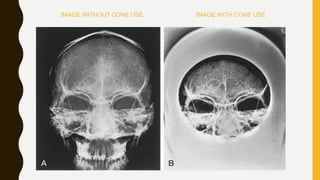

IMAGE WITHOUT CONE USE. IMAGE WITH CONE USE

IMAGE WITHOUT CONEUSE. IMAGE WITH CONE USE